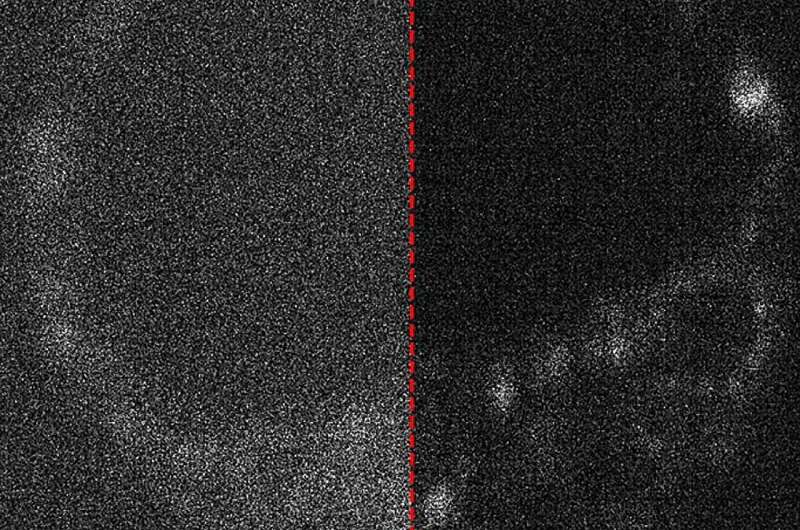

“A lot of natural compounds in cells light up when illuminated, and this can tell us a lot about what we’re looking at, but unfortunately the signal is very weak,” he said.

“A large part of the project involved developing a method to fairly compare the image quality across different cameras.”

“We even explored how AI can be used to remove noise from the captured images, which is essentially static because the camera struggles to capture enough light,” said Peterkovic.